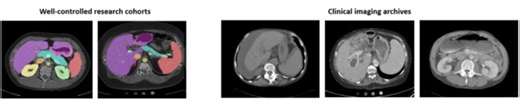

Validation and Optimization of Multi-Organ Segmentation on Clinical Imaging Archives

vanderbilt.edu

2020年2月12日

Validation and Optimization of Multi-Organ Segmentation on Clinical I

…